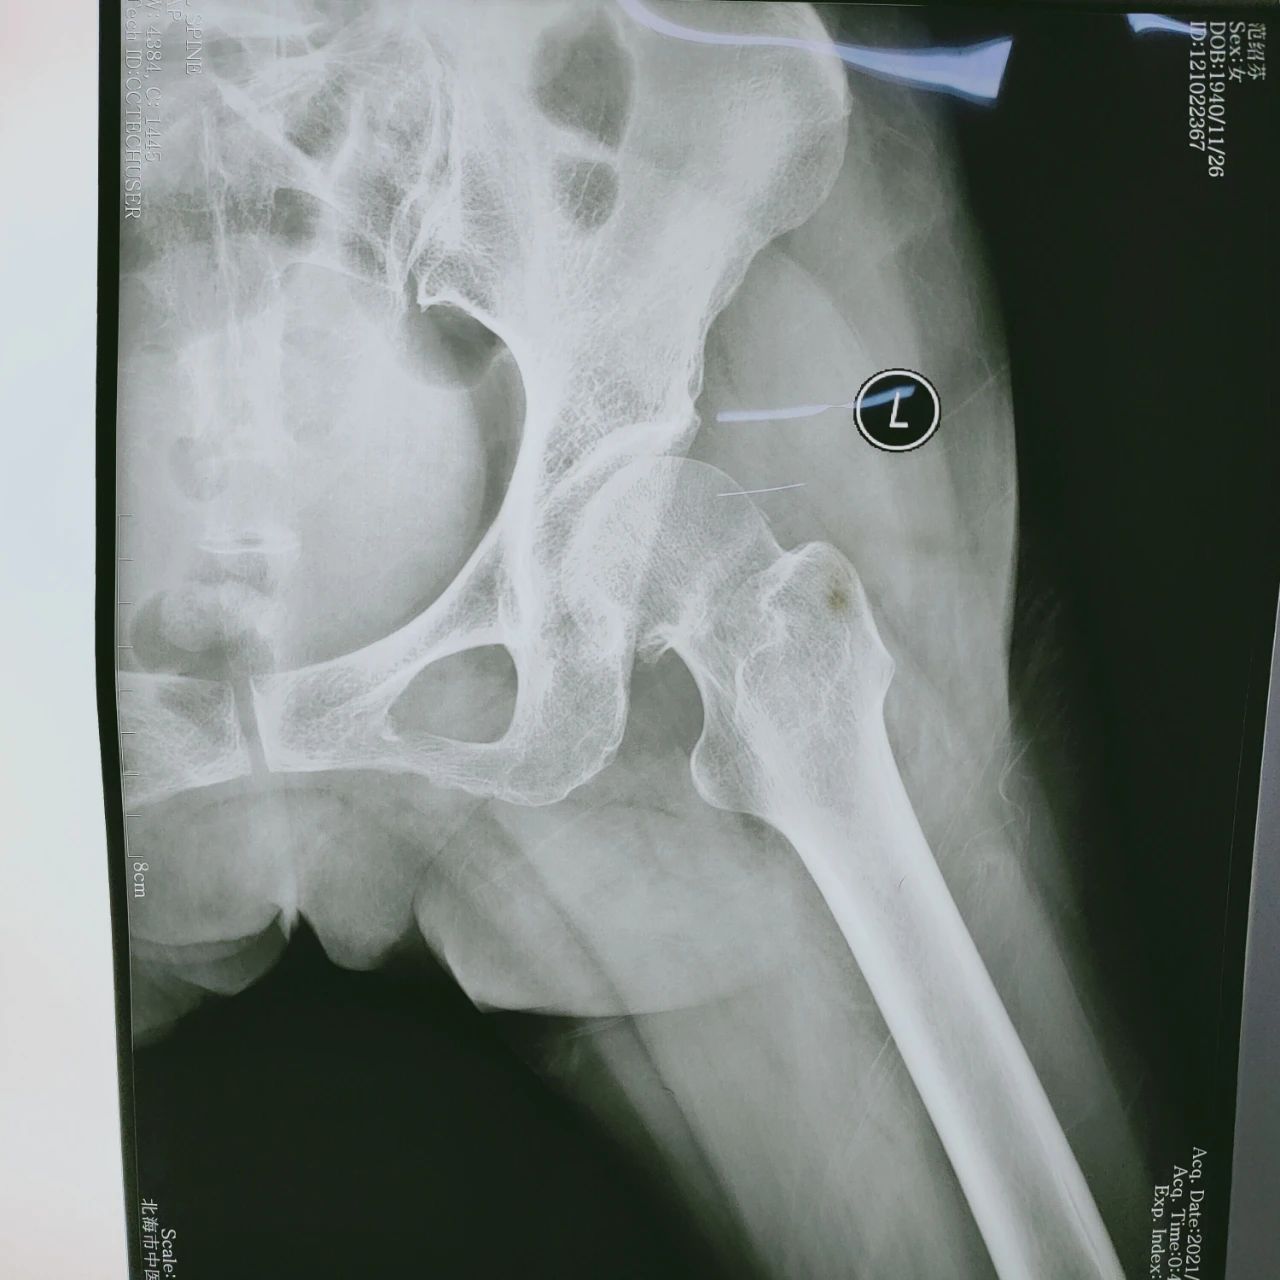

患者为80岁老年女性,因跌伤致股骨颈骨折而入院。因该病人为高龄患者,且长期患有高血压等基础疾病及机体功能退变,如果选择非手术治疗方案,患者需要卧

床长达3-6个月时间,容易并发肺炎、泌尿系统感染等。为了使患者能够尽快恢复肢体功能,提高生活质量,骨伤科二病区专家经讨论,为患者制定了实施微创髋